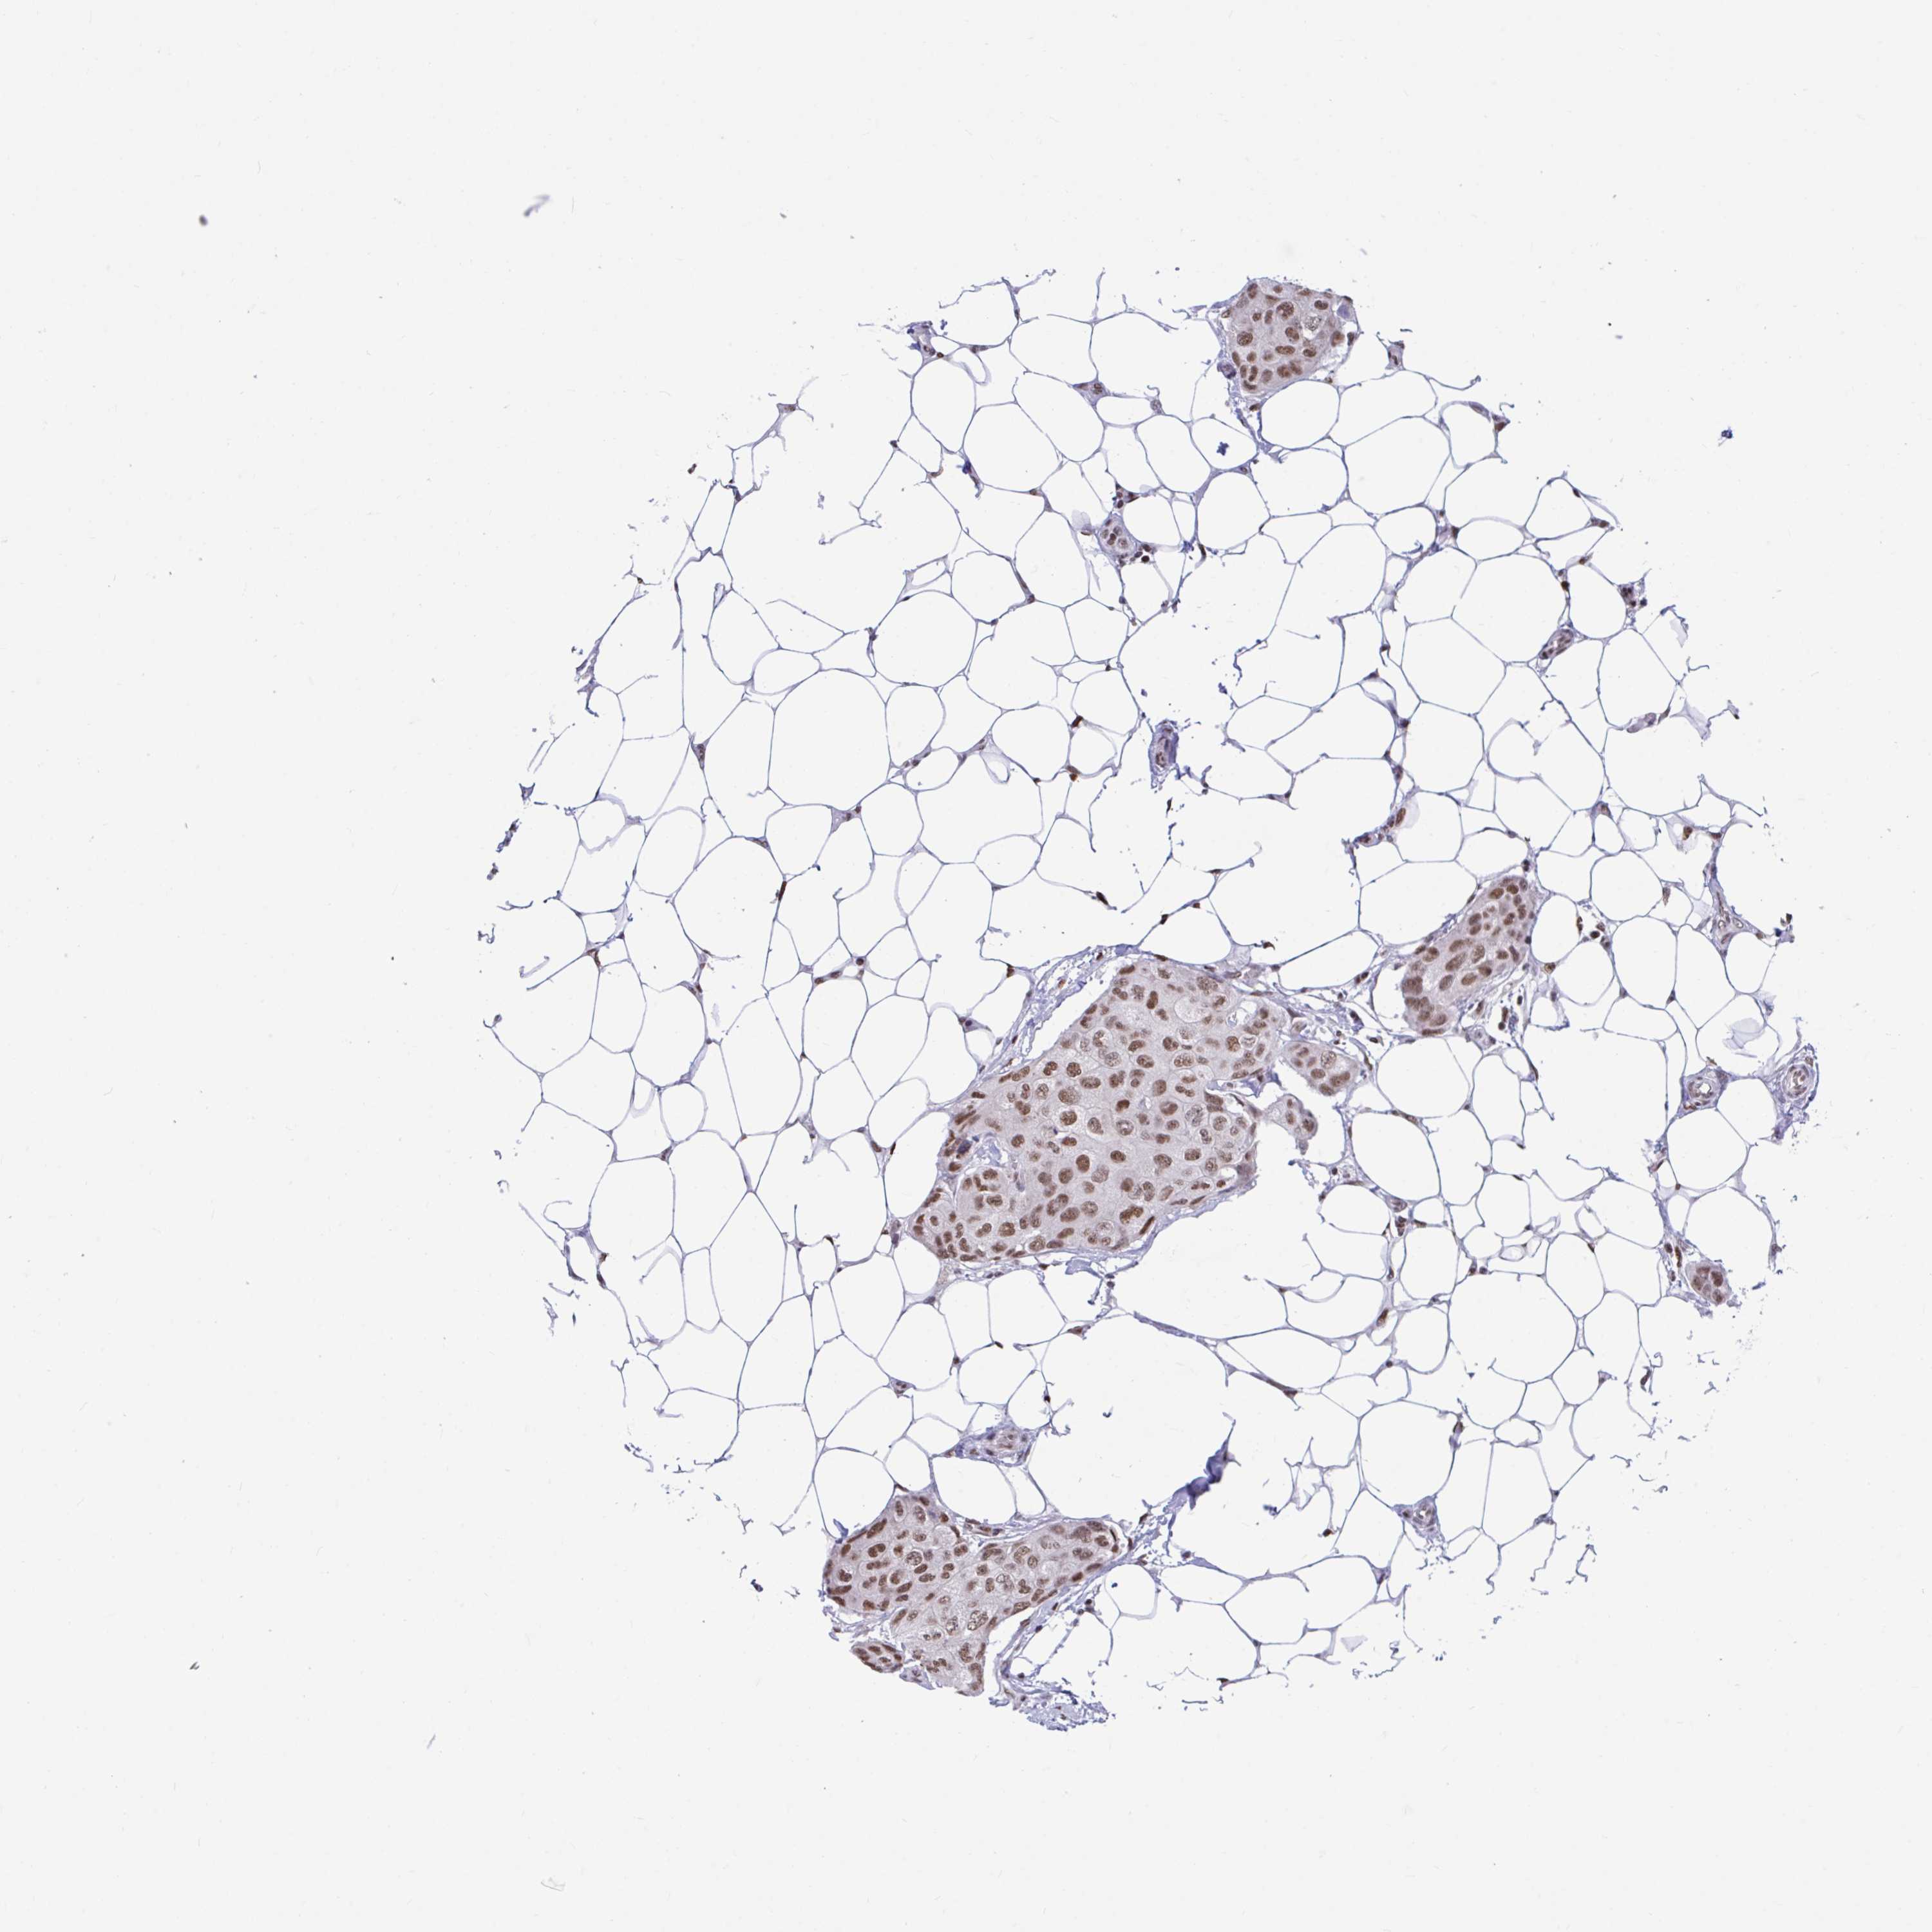

CANCER BREAST CANCER Show tissue menu

BRCA TCGA BRCA VALIDATION PROTEIN EXPRESSION